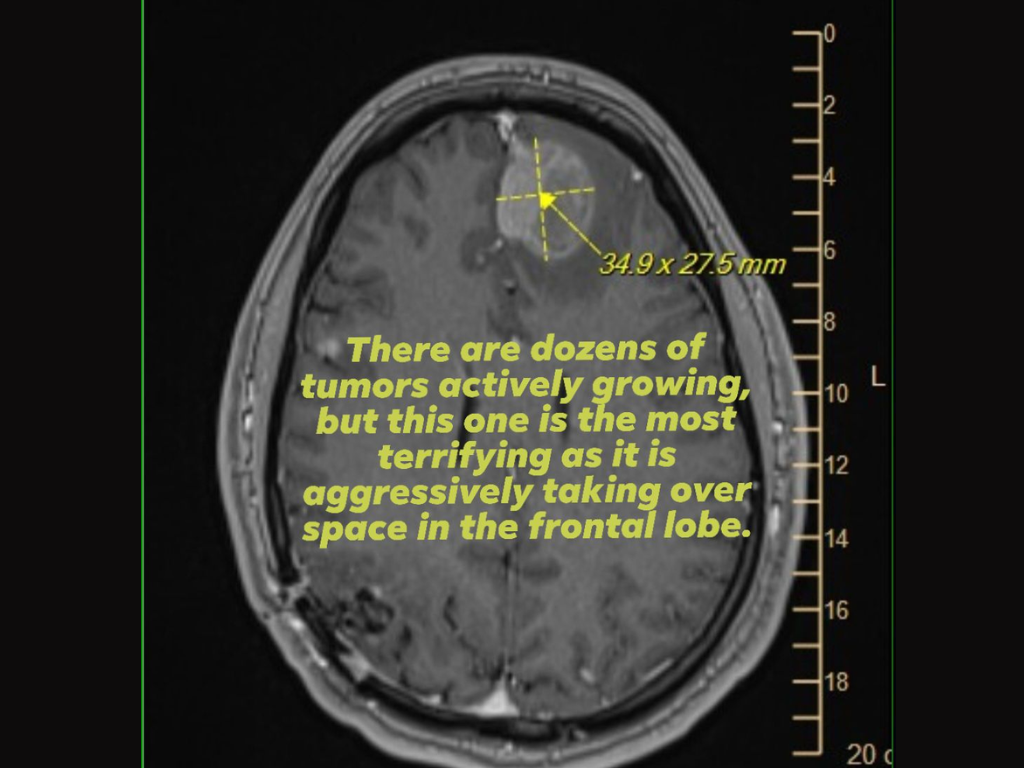

Pour preuve, elle a également joint une image d'un scanner cérébral (IRM) montrant une tumeur agressive du lobe frontal, tout en implorant le soutien ou l'aide des cadres d'Epic Games, qui ont pris les décisions clés concernant les licenciements.